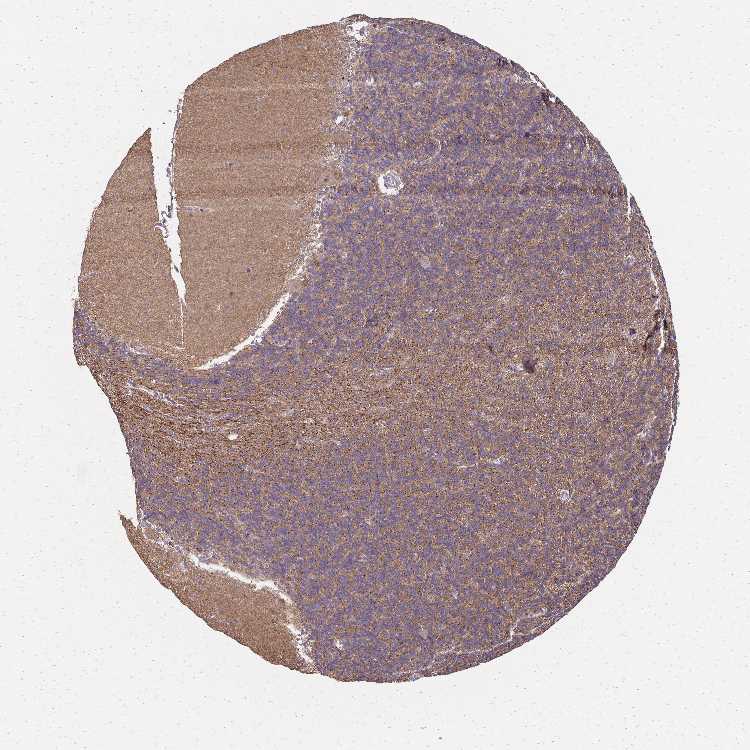

CEREBELLUM - Antibody stainingi

Antibody staining in the annotated cell types in the current human tissue is reported as not detected, low, medium, or high, based on conventional immunohistochemistry profiling in selected tissues. This score is based on the combination of the staining intensity and fraction of stained cells.

Each image is clickable and will lead to virtual microscopy that enables deeper exploration of all samples and also displays staining intensity scores, fraction scores and subcellular localization as well as patient and tissue information for each sample.

Antibody HPA045599

Bergmann glia - cytoplasm/membrane Not detected

Bergmann glia - nucleus Not detected

GLUC cells - cytoplasm/membrane Not detected

GLUC cells - nucleus Not detected

Purkinje cells - cytoplasm/membrane Not detected

Purkinje cells - dendrites Not detected

Purkinje cells - nucleus Not detected

Granular cells - cytoplasm/membrane High

Granular cells - nucleus Not detected

Molecular layer - neuropil Medium

Molecular layer cells - cytoplasm/membrane Not detected

Molecular layer cells - nucleus Not detected

Processes in granular layer Not detected

Processes in molecular layer Not detected

Processes in white matter Not detected

Synaptic glomeruli - capsule Not detected

Synaptic glomeruli - core Not detected

White matter cells - cytoplasm/membrane High

White matter cells - nucleus Not detected